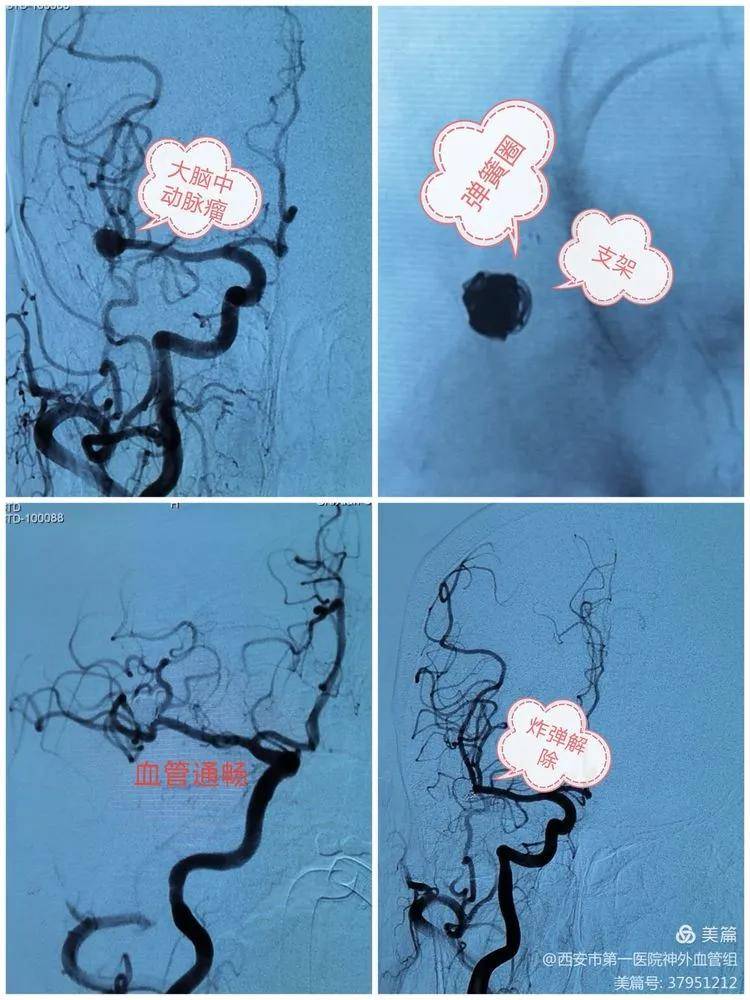

文章图片

时隔1周 , 又一位60岁大妈突发头痛来院 , 头颅CT提示大脑中动脉瘤 , 遂急诊支架辅助栓塞 , 动脉瘤位于血管分叉处 , 血管转角大 , 既要消灭动脉瘤 , 又要保住血管 , 我们以精湛技术再次成功"拆弹" , 患者术后完全正常!